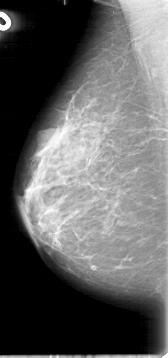

D_4057_1.LEFT_CC

LEFT_CC LINES 5296 PIXELS_PER_LINE 3256 BITS_PER_PIXEL 12 RESOLUTION 43.5 OVERLAY